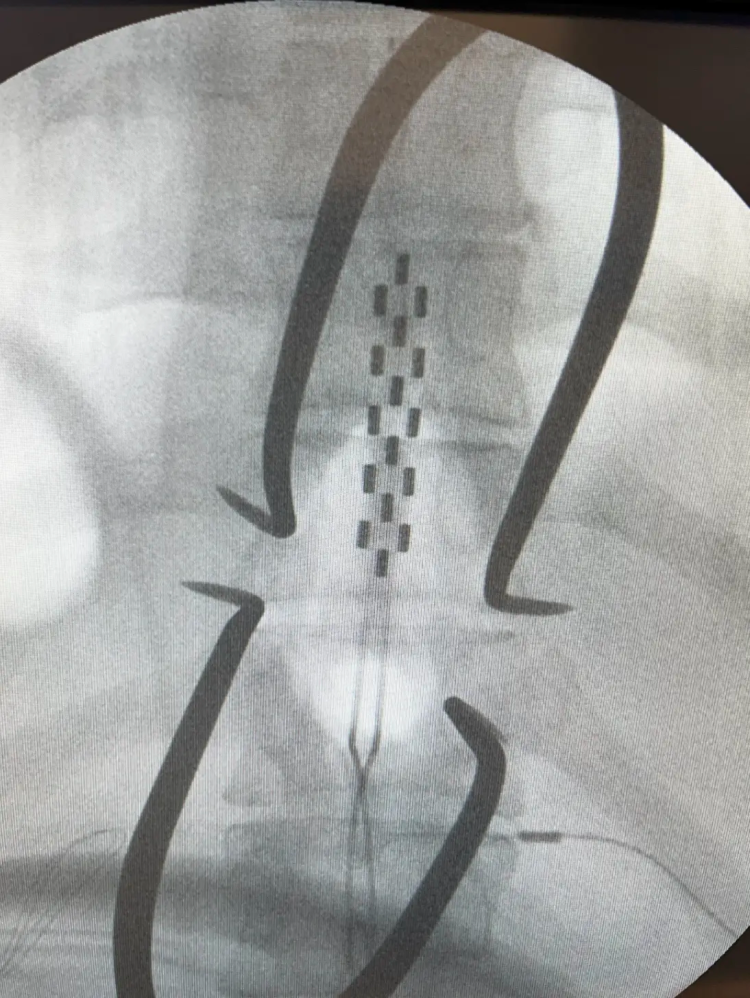

An electrode placed in the epidural space of the spine stimulates the spinal cord. Photo Courtesy Phillips Lab